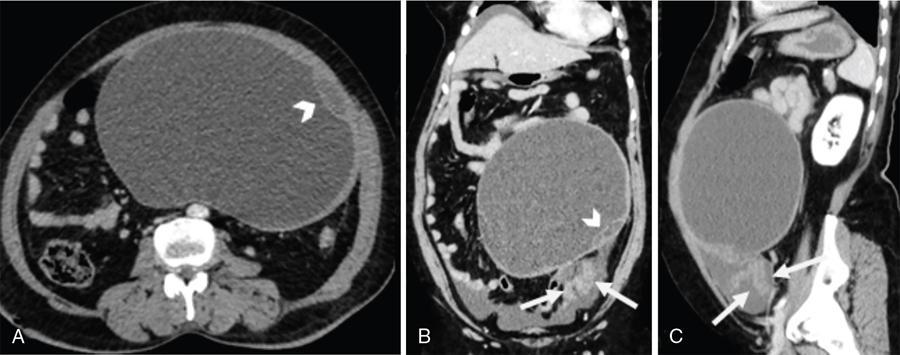

Fig. 11.16.1.2 Benign serous cyst with torsion in a 52-year-old postmenopausal lady presenting with acute left-sided abdominal pain. (A) Axial CT section with (B) coronal and (C) sagittal reformations shows a large cyst in the central and left lower abdomen with few septae within (arrowheads). (B and C) An enhancing thickened twisted pedicle is noted extending from the pelvis up to the cyst (arrows). Surgery and histopathology confirmed features of benign serous cyst with torsion.